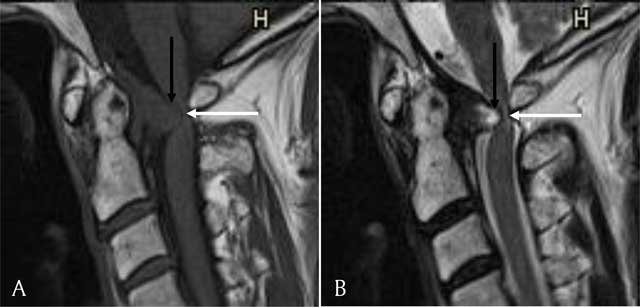

Figure 2

(A) Sagittal T1-weighted image. The retro-odontoid pseudotumor is seen as a mass (black arrow) extruding through the transverse ligament and compressing the myelum (white arrow). It has an isointense signal compared to the myelum. (B) Sagittal T2-weighted image. The retro-odontoid pseudotumor has a hyperintense signal (black arrow) and compresses the myelum (white arrow).